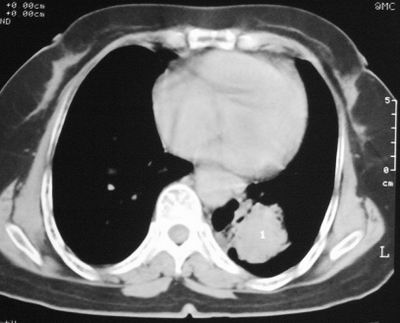

患者,女,64岁,4年前左腮腺"多形性"腺瘤手术治疗史.现复查胸部ct见左下肺块状影,该影与原左腮腺手术是否有联系?

本次复查胸部ct

左下肺软组织块影,有分叶、毛刺、空泡及胸膜牵拉征,左下肺周围性肺癌。

我考虑炎性假瘤:1,边界模糊.2,邻近胸膜增厚,胸膜外脂肪也增厚.3,周围有肺气肿征.4,无胸水,无淋巴结肿大.

左肺下叶周围型肺癌,支持!(软组织肿块+分叶+毛刺+空泡+胸膜凹陷征)

肿块周围提示慢性改变,邻近胸膜外脂肪有沉积,考虑为良性,炎性假瘤可能。

左下肺软组织密度影,可见分叶,边缘可见毛刺征,胸膜增厚,强烈要求左下肺周围型肺癌

左下肺后基底段实性肿块,周围有毛刺,病变周围有肺气肿,与降主动脉间有条带状影相连,病灶4年前查体发现,纵隔内未见肿大淋巴结。考虑.肺隔离症,建议增强扫描与周围型肺癌鉴别。